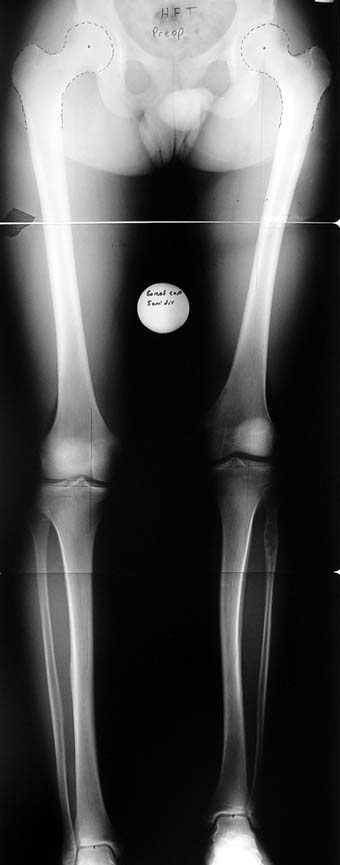

Many patients don’t want to use a shoe support thicker than 2 cm. For length differences between 2 cm and 5 cm, shortening may be considered for tall patients. This can be performed in growing children with a small, minimally invasive, uncomplicated procedure called epiphysiodesis. This means surgical disruption of one or more growth plates. There is a growth plate at the ends of femur, tibia and fibula; this procedure does not halt all growing of the leg. The growing of the longer leg is calculated and halted to allow the shorter leg to catch up.If the procedure is performed at a too early or too late age, the correction may be too much or too little, respectively. Hence, it is important to accurately calculate the most appropriate age for epiphysiodesis. When and at which bone segment epiphysiodesis will be performed shall be calculated by the doctor using different methods such as Gren-Anderson diagram, Moseley curve or Paley’s multiplier method.Epiphysiodesis is not an option for adults because growth plates ar closed. In adults, a bone segment has to be excised surgically in order to shorten the leg. This is usually performed at femur and bone is later fixed with an intramedullary nail. The biggest advantage of this system is that it acutely provides limb length equality for discrepancies less than 5 cm. The common disadvantage of epiphysiodesis and shortening is the shortening of total height of the patient. Because we don’t advice shortening more than 5 cm, height loss can’t be more than 5 cm. For patients who don’t want an epiphysiodesis or shortening operation for length inequalities less than 5 cm, limb lengthening can be preferred in order to equalize the length difference.This can be combined with epiphysiodesis and shortening to decrease a need for another lengthening operation or to decrease the lengthening amount required.

3. POSTTRAUMATIC LOWER LIMB SHORTNESS (MALUNION)

This type of shortness occurs after a fracture heals in a shortened position. Most cases are seen in adults and can be treated with one lengthening operation. Additional deformities can be corrected simultaneously. Most of these cases can be treated with lengthening over nail or just corrections and intramedullary nailing.